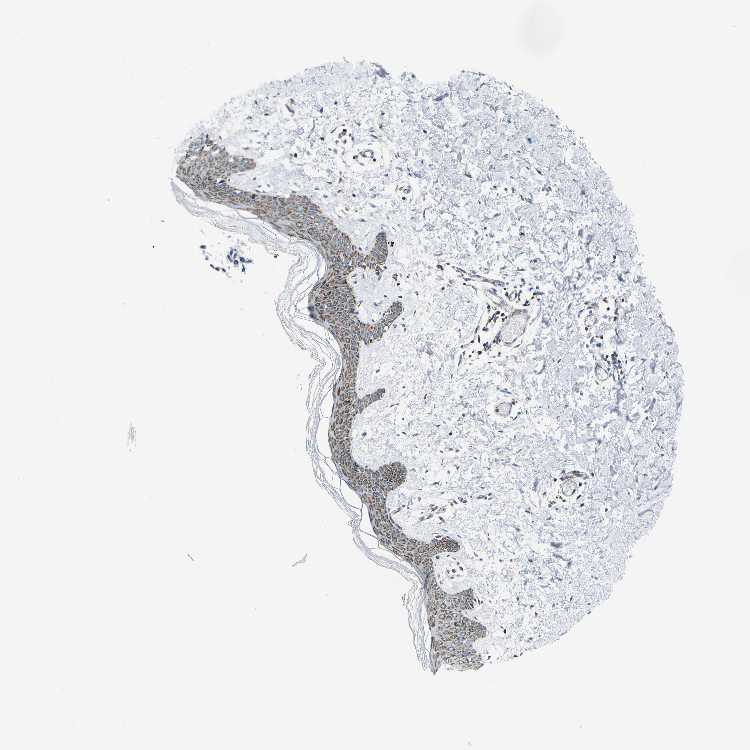

SKIN 1 - Antibody stainingi

Antibody staining in the annotated cell types in the current human tissue is reported as not detected, low, medium, or high, based on conventional immunohistochemistry profiling in selected tissues. This score is based on the combination of the staining intensity and fraction of stained cells.

Each image is clickable and will lead to virtual microscopy that enables deeper exploration of all samples and also displays staining intensity scores, fraction scores and subcellular localization as well as patient and tissue information for each sample.

Antibody HPA014295Antibody CAB016244

Langerhans -High

Cells in basal layer Medium-

Cells in corneal layer Not detected-

Cells in granular layer Medium-

Cells in spinous layer Medium-

Eccrine glands Medium-

Endothelial cells Medium-

Extracellular matrix Not detected-

Fibroblasts -Not detected

Fibrohistiocytic cells Medium-

Keratinocytes -High

Langerhans cells Medium-

Lymphocytes High-

Melanocytes MediumHigh

Vascular mural cells Not detected-

SKIN 2 - Antibody stainingi